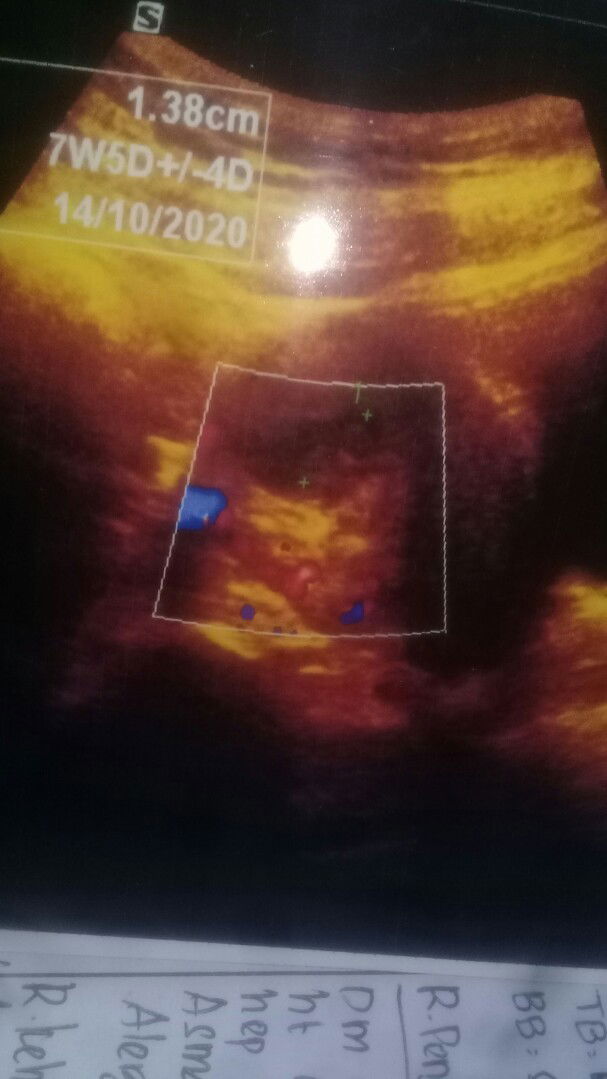

flek :(

Bund aku ngeflek selama 10hari kehamilan anak pertama tp jarang2 darahnya kluar dan itu aku USG detak jantungnya blm kedengeran dan dokter bilang janin ku tdk berkembang dan aku dikasih penguat & tunggu selama 1minggu ini perkembangannya . Aku periksa dibidan usia janin ku 11week tp kmren aku periksa didokter 7w5d . Kalau bunda jd aku bgmn hrus menyikapinya / mngambil tindakan yg bgmn ? ? Dan kalau bunda lihat janin ku bgmn ?